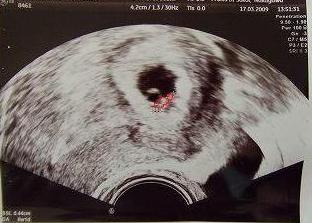

| 初診:0317 091110予 尿検査 6w1d:0.44cm |

|

頭臀長:0.44cm クリオネ見たいだったw 心臓バクバクしてるのが見えた つわりあり:胸やけ・嘔吐・胃痛 便秘軟便・ゲップ・下腹部つっぱる痛みあり 出血なし(子宮が大きくなってるからとのこと) ダルさ・疲れやすい |